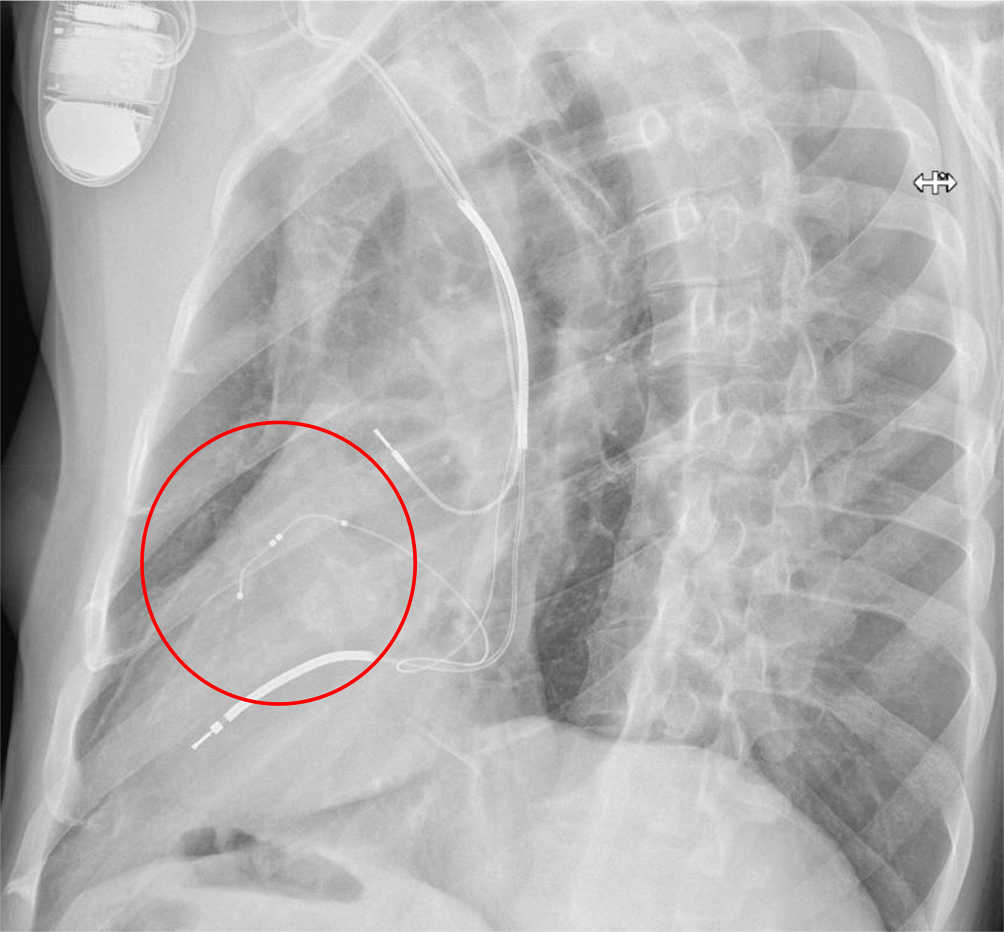

Abb. 10

Laterale Röntgenaufnahme des Thorax, die eine unbefriedigende anteriore Position der LV-Elektrode zeigt (roter Kreis). Diese Position ist insbesondere mit einem schlechten Ergebnis der CRT verbunden